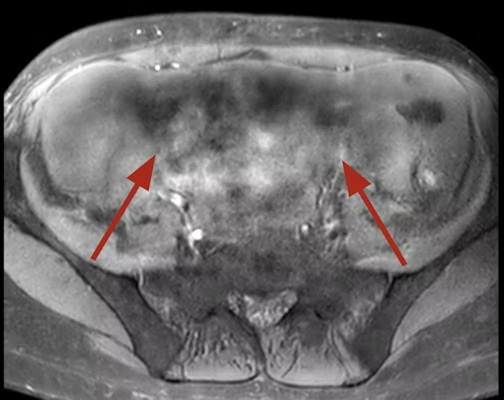

There are several types of MRI artifacts that beginners should know about. One common type is motion artifacts, which happen when a patient moves during the scan. Another type is metal artifacts, caused by implants or metal objects in the body. Other types include ghosting, aliasing, and susceptibility artifacts. Each type affects the image in a different way, making some areas appear blurry, distorted, or even missing.

MRI artifacts can occur due to multiple reasons. Patient movement is one of the main causes, as even small movements like breathing or swallowing can create motion artifacts. Technical factors such as incorrect scan settings or hardware issues can also contribute. Additionally, the presence of metal in the body, like dental fillings or surgical implants, can distort the magnetic field, creating noticeable artifacts on the image.

The presence of MRI artifacts can significantly impact image quality and the accuracy of diagnosis. Blurred or distorted areas can make it difficult for doctors to see small but critical structures, such as blood vessels or tumors. In some cases, artifacts may mimic disease, leading to unnecessary tests or procedures. This is why understanding and minimizing artifacts is crucial in medical imaging.